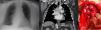

(a) Image of the mediastinal mass on chest X-ray. (b) Image of chest CT showing the mass in the middle mediastinum. (c) Paraganglioma during surgery, seen in the center of the image. The trachea is located at the top and the innominate vein is above it. The aorta is on the right and the pulmonary artery trunk below.

A 74-year-old woman was referred to the respiratory medicine department with an incidental finding of a mediastinal mass on a chest X-ray (Fig. 1a). She was asymptomatic and the physical examination showed no findings of interest.

A chest CT scan revealed a hypervascularized mass measuring 48 × 43 mm in the mediastinum displacing the trachea, esophagus, ascending aorta, and right hilum (Fig. 1b), so a differential diagnosis was performed between paraganglioma, Castleman disease, vascular malformations, and metastases.1

An octreotide scan and a functional study were subsequently performed, establishing a diagnosis of non-functioning paraganglioma of the mediastinum. Surgical resection was performed via middle sternotomy (Fig. 1c) with pre-embolization.